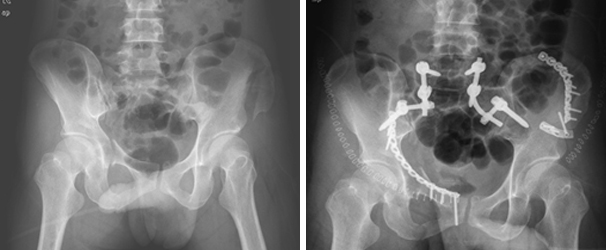

골반환 골절 및 장골 골절의 내고정술 골반환 골절 및 장골 골절의 내고정술 이미지